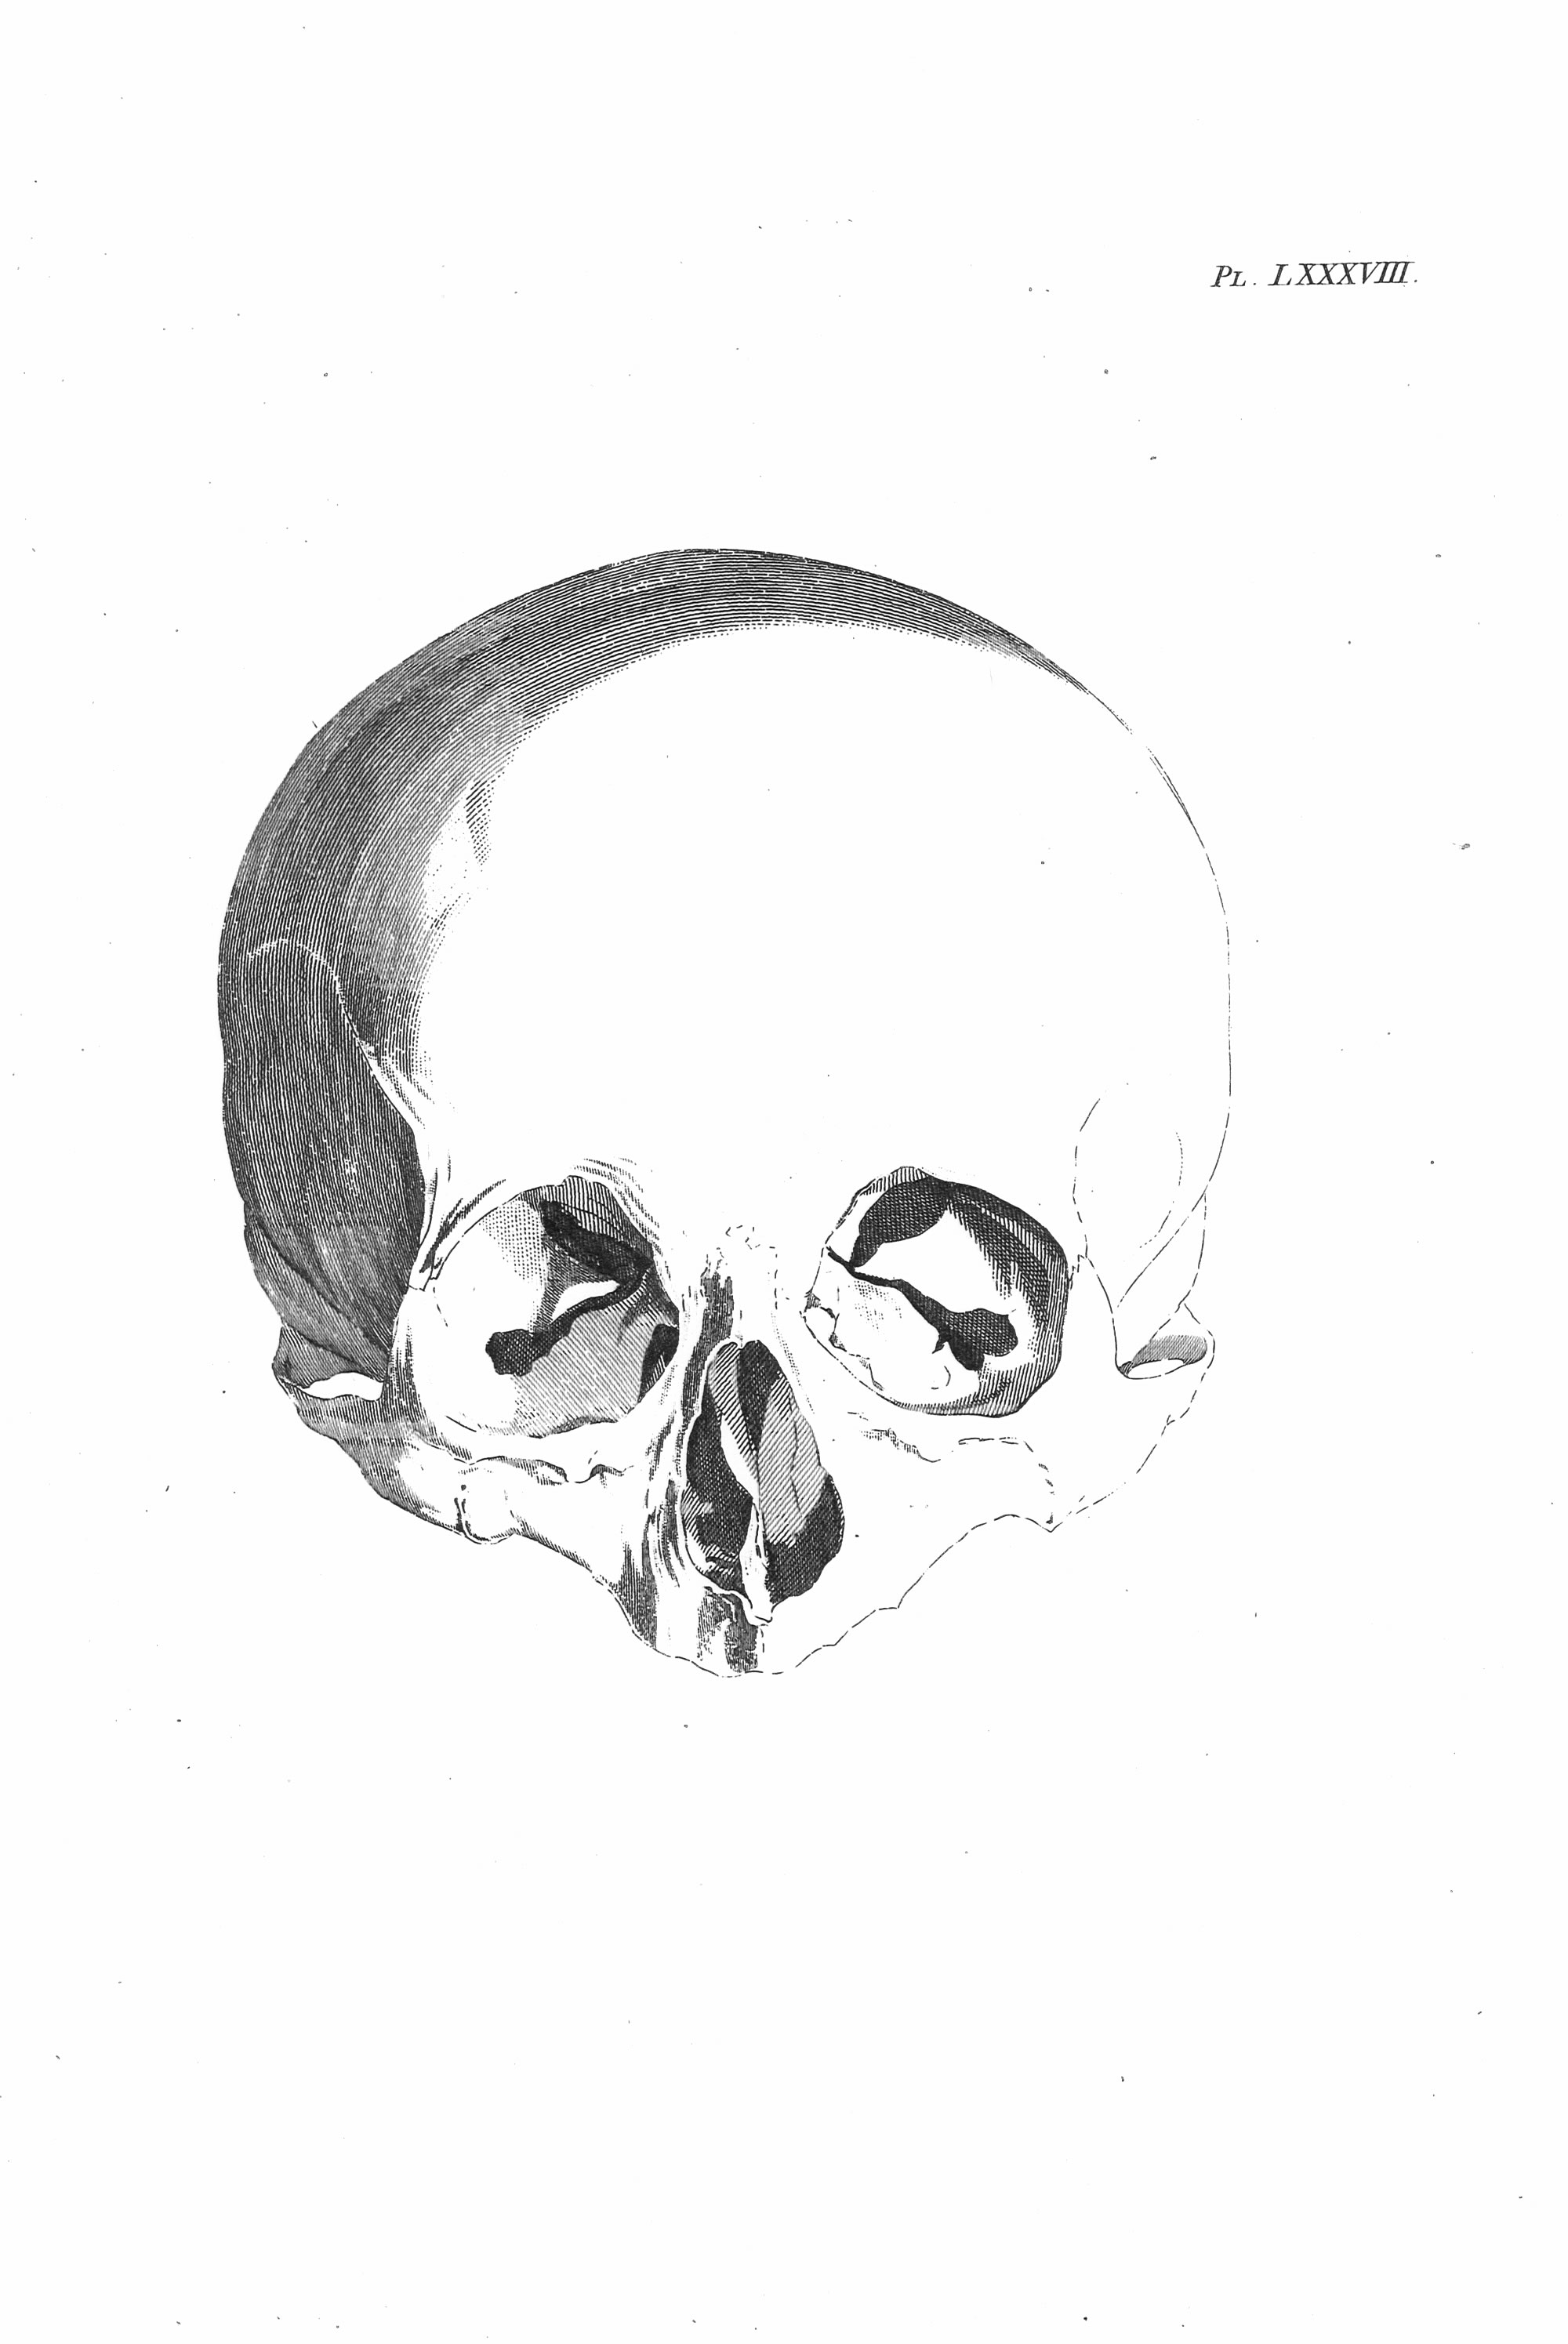

Gall, F. J. (1818). Anatomie et physiologie du système nerveux en général, et du cerveau en particulier, Avec des observations sur la possibilité de reconnoître plusieurs dispositions intellectuelles et morales de l´homme et des animaux, par la configuration de leurs têtes.

Librairie Grecque-Latine-Allemande, Vol. 3, I-XXXV u. 1-379 100 planches.